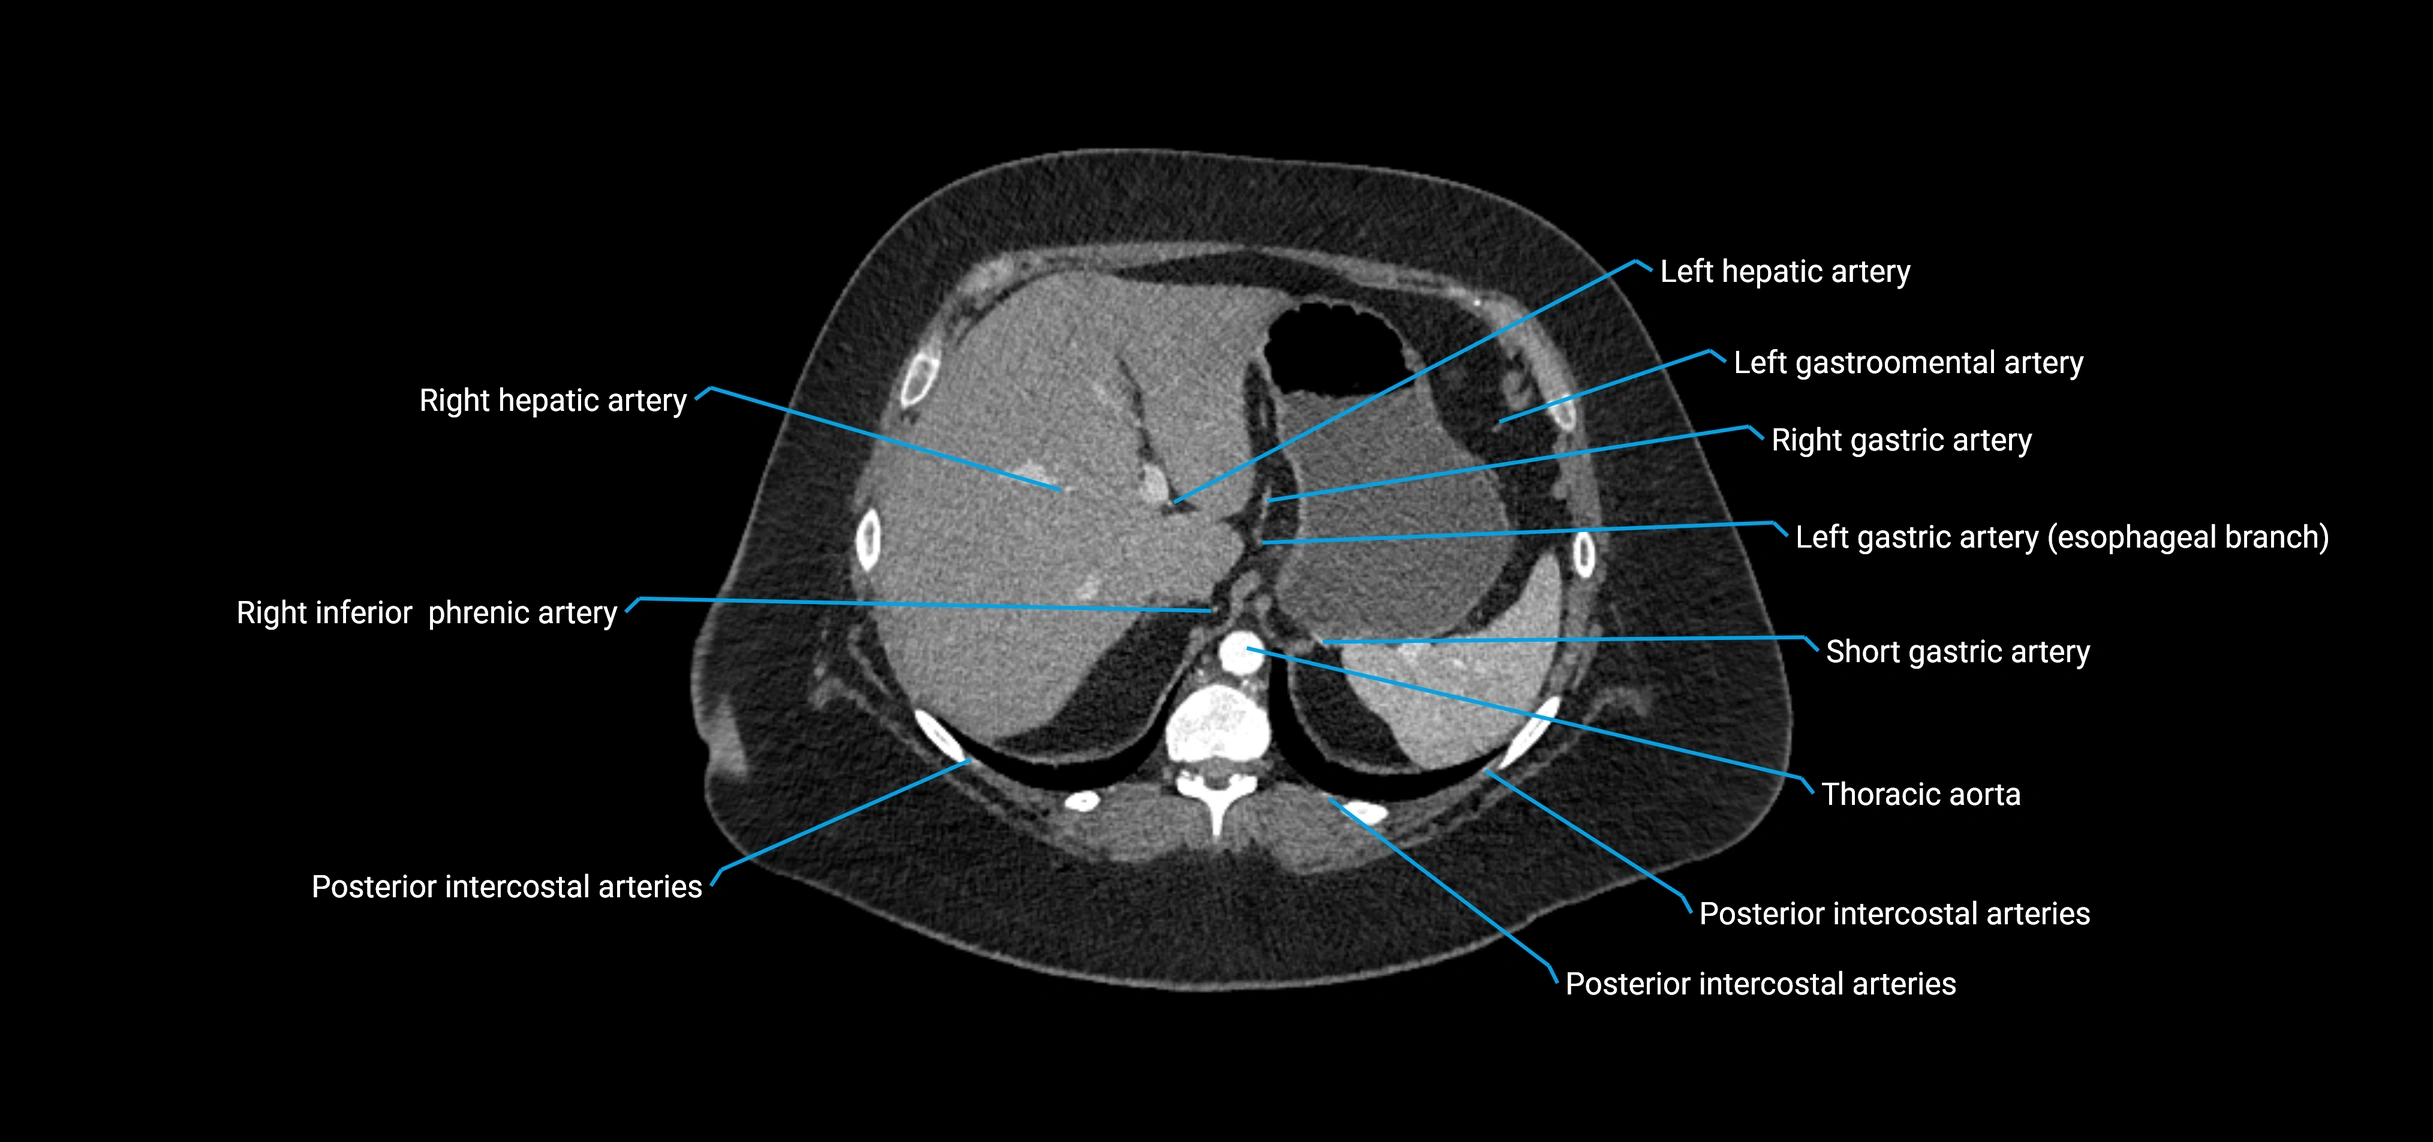

MRI Appearance

T1-weighted images:

• Flowing blood appears as a signal void (black lumen)

• Vessel wall appears as a thin hypointense rim; retroperitoneal fat enhances contrast

T2-weighted images:

• Lumen remains a signal void due to flow

T1 Post-Contrast (Gadolinium-enhanced):

• Aortic lumen enhances brightly and homogeneously

• Clearly demonstrates aneurysm, stenosis, dissection, mural thrombus, or aortic wall enhancement in vasculitis

MRA (Magnetic Resonance Angiography):

• Contrast-enhanced MRA provides high-resolution imaging of the aorta and its branches

• Allows 3D reconstruction of visceral, parietal, and terminal branches

• Excellent for evaluating aneurysm size, dissection flap, stenosis, or preoperative planning

• Non-invasive alternative to conventional angiography